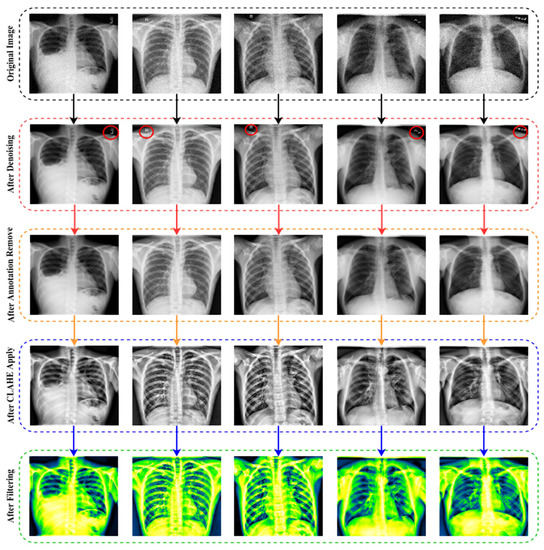

- The raw chest X-ray data for the study is collected from multiple data sources, merged into a collective dataset. To ensure all the data are in the same scale, preprocessing is performed.

- Autoencoder is employed to denoise the noisy images. For removing annotation in the data, the EnsNet method is used.

- CLAHE enhancement methods are used to increase the quality of the X-ray images, and the Green Fire Blue filtering technique is applied to improve the image properties and make them more identical to the model.